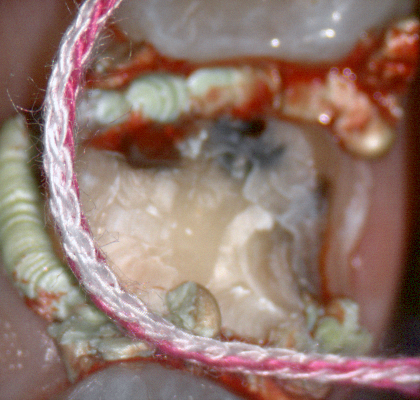

A shoulder bur of .8 mm thickness can help you reduce the interproximal areas as well as the buccal and lingual margin lines. Before finishing the prep, place hemostatic agent like expasyl in the sulcus and place retraction cord. while it is setting, check your reduction. If you need more space, now is the time to reduce some more.